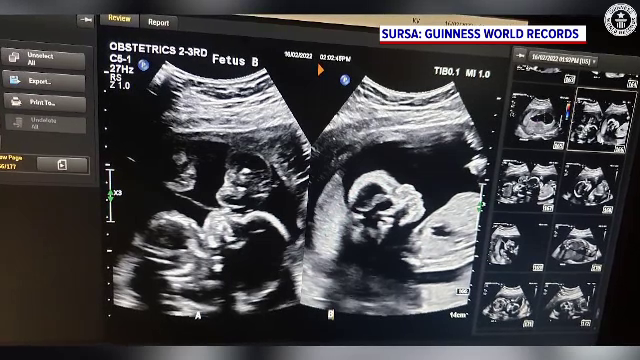

Doi bebelusi din Canada au intrat in Cartea recordurilor cu titlul de "cei mai prematuri gemeni supraviețuitori" din lume.

Adiah și Adrial Nadarajah s-au născut la numai 126 de zile, adică la 22 de săptămâni de sarcină.